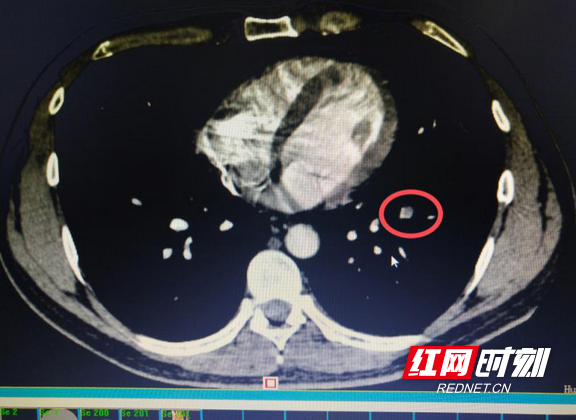

患者肺动脉CT显示“肺栓塞”位置。

呼吸及危重症医学科主任曾祥伯副主任医生在门诊接诊了该患者,根据患者的临床表现和近期手术制动病史,高度怀疑为肺栓塞合并肺梗死,立即让患者住院,避免剧烈活动以免病情进一步加重,并带患者进行了肺动脉CTA检查。很快,CTA确诊赵先生是发生了“急性肺栓塞”。

目前肺栓塞的诊断主要依靠肺动脉CT造影。肺栓塞的治疗主要是要使栓塞的肺动脉再次开通,根据病情严重程度及危险因素分层,医生决定使用药物溶栓或者抗凝治疗,特殊情况下需要采用手术治疗。确诊规范治疗后,绝大多数患者都能够治愈。